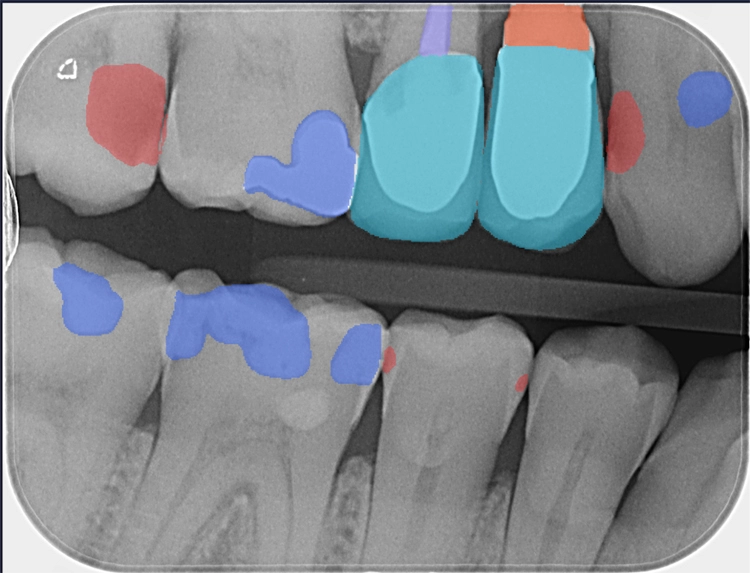

Falls gewünscht, können die maschinell detektierten Befunde vom Behandler angepasst oder ergänzt werden. Anschließend stehen Befund und Therapieempfehlung für das Patientengespräch bereit. Da dentalXrai die Detektion farblich hervorhebt, ist sie auch für den Patienten am iPad verständlich und nachvollziehbar (Abb. 3–6). Ein automatisch erstelltes Gesprächsprotokoll mit der dentalXrai-Befundung kann dem Patienten ganz einfach per verschlüsselter Mail geschickt werden.

dentalXraiAbb. 3–6: Der Vergleich von nativem Röntgenbild (am Beispiel von OPG und Bissflügelaufnahme verschiedener Patienten) und dem Bild mit eingeblendeten Detektionen zeigt die Gründlichkeit der KI-Befundung. Die befundeten apikalen Läsionen sind orangefarben markiert, die Karies rot. Bestehende Versorgungen sind blau und türkis hervorgehoben. Die Zahnsituation ist so für den Patienten im Gespräch gut nachvollziehbar und auch in der Nachbereitung zuhause immer wieder gut zu erkennen.

Pathologische Befunde sind in Rot- und Orangetönen markiert, die bisherige ZE-Versorgung, Restaurationen, Wurzelkanalfüllungen, Implantate etc. in Blautönen. Über die Bedienleiste kann auch die Editierfunktion aufgerufen werden, um z.B. einen Befund noch manuell zu bearbeiten. Der fertige Befundbericht inklusive einer Liste der Detektionen je Quadrant wird dann in der Praxisverwaltungssoftware (PVS) gespeichert.